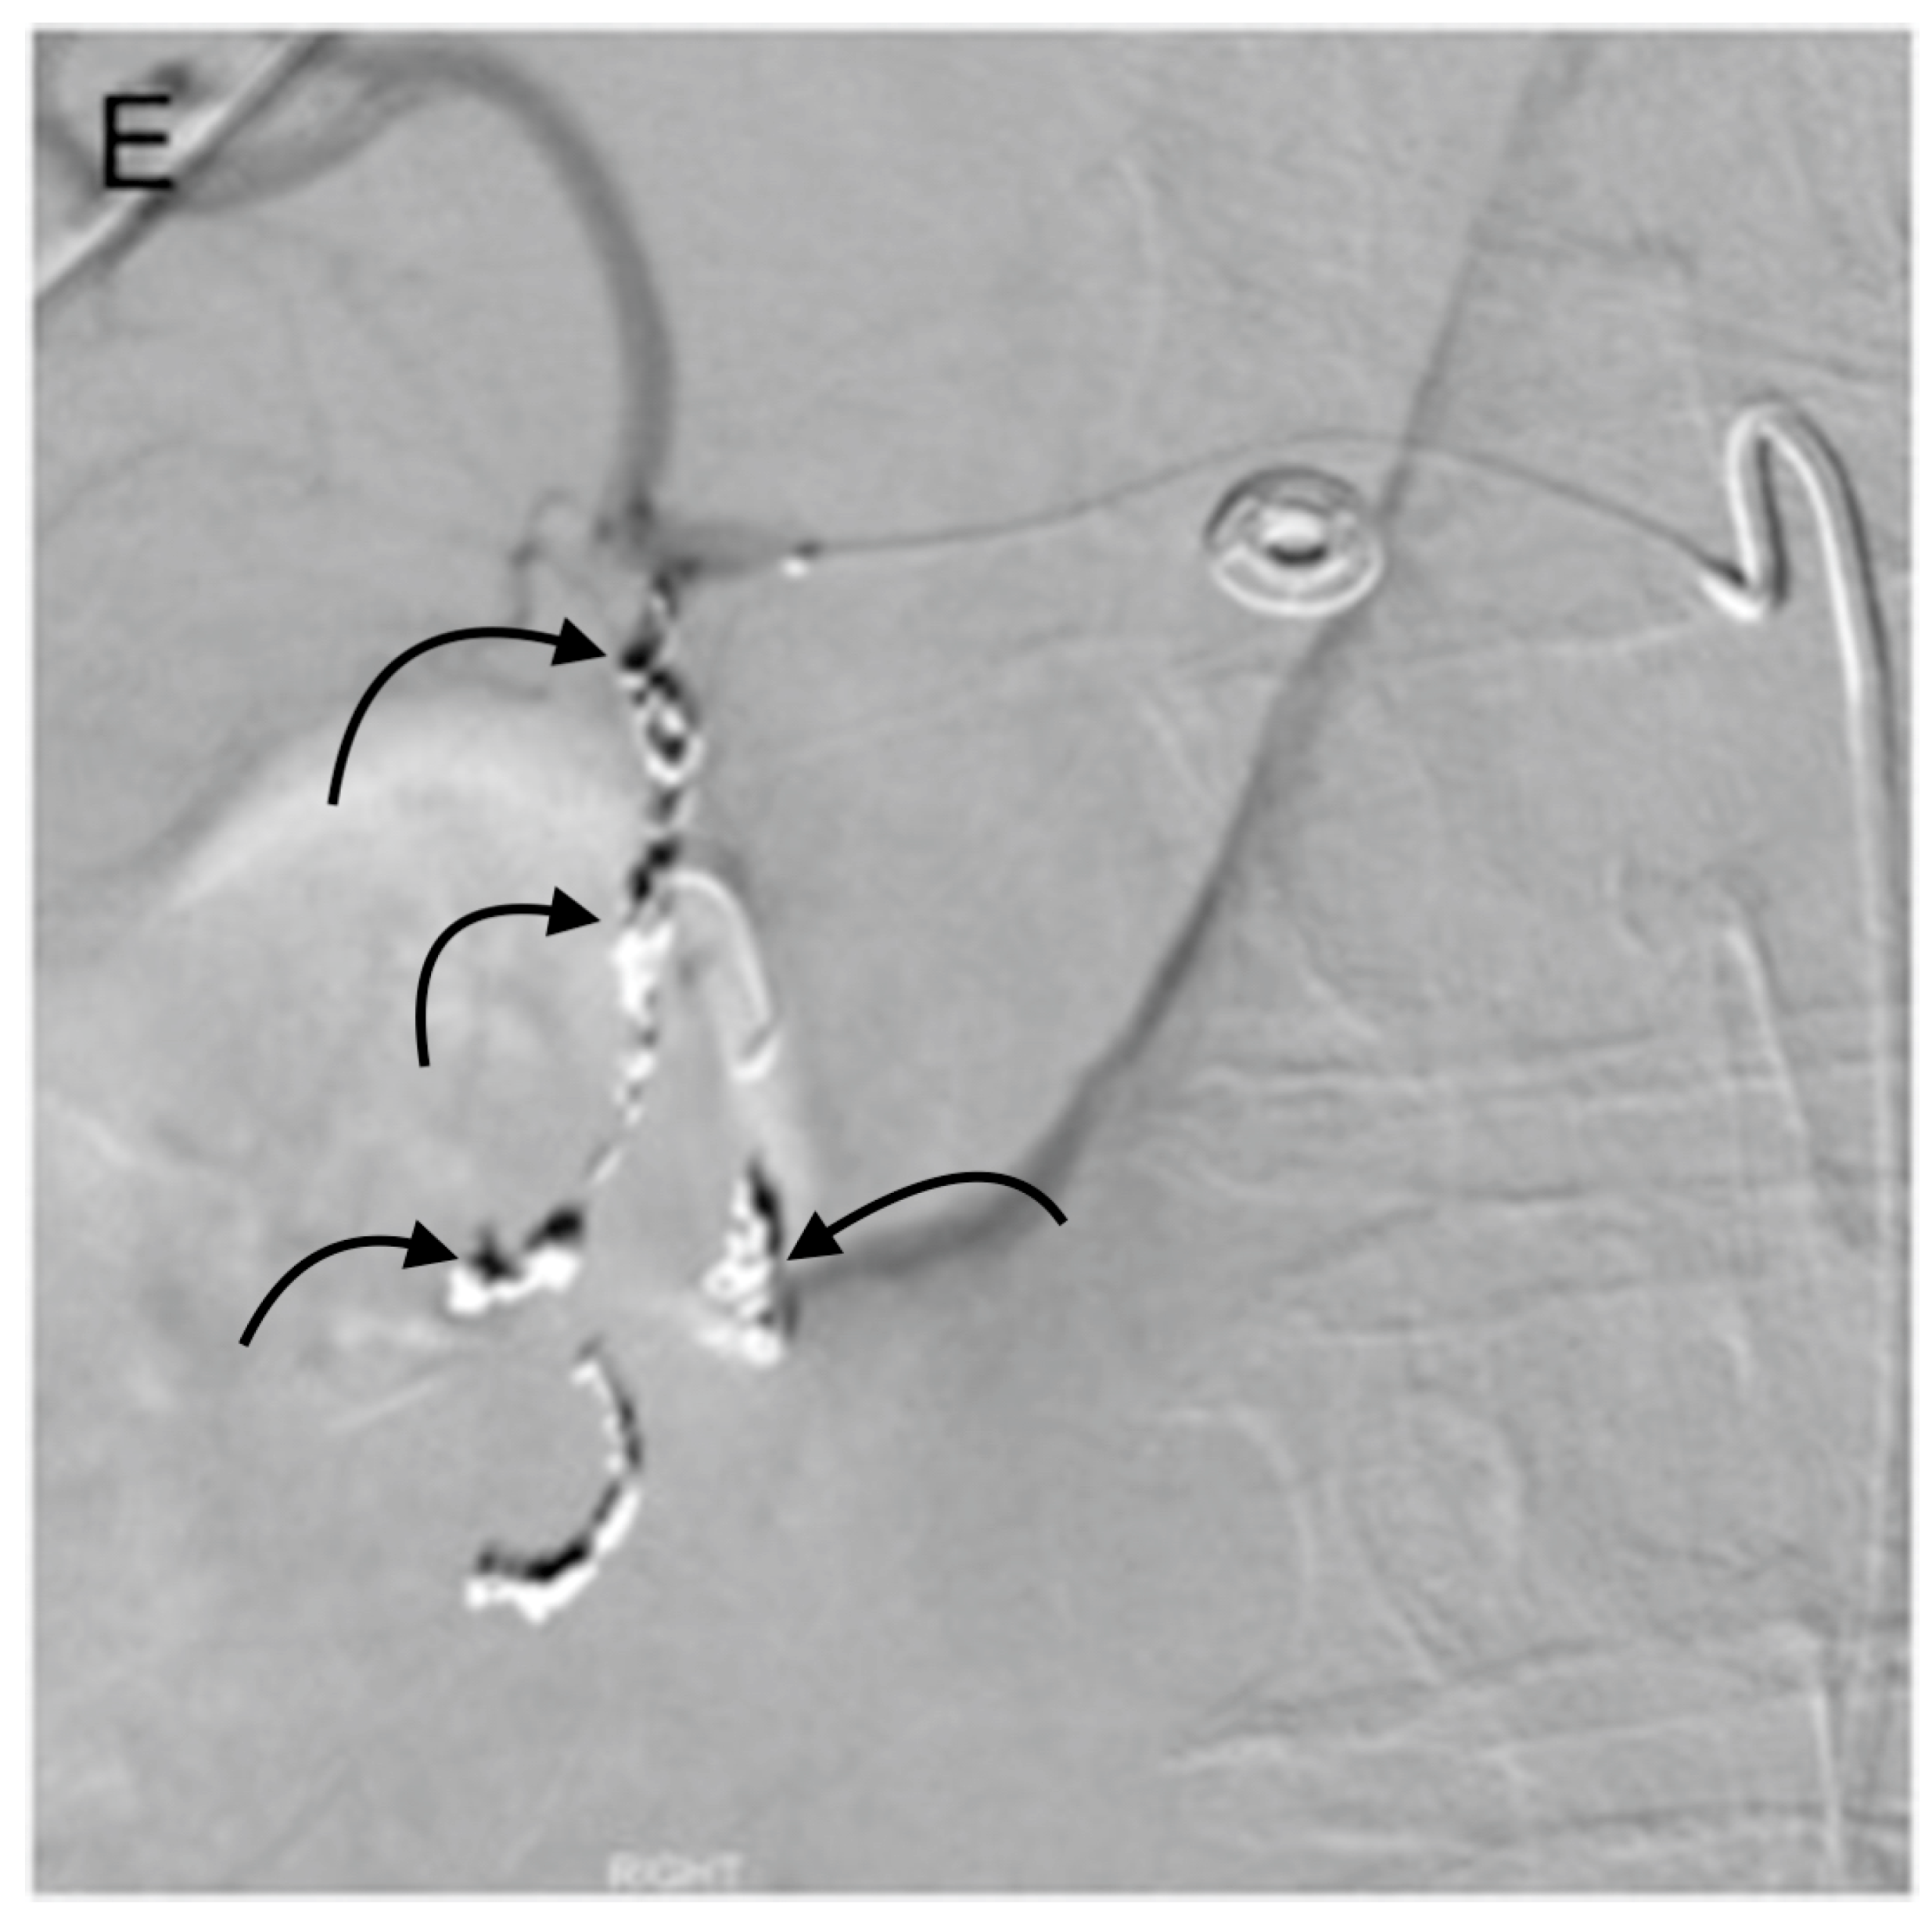

3. GDA Embolization in Gastrointestinal Bleeding

4. GDA Pseudoaneurysm Embolization

5. Pre-Y-90 GDA Embolization